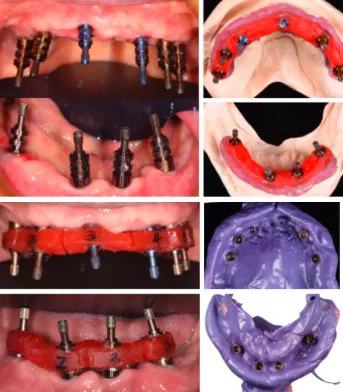

- 依据患者CBCT和口内模型,制作放射导板,患者戴入放射导板,拍摄CBCT,

- 通过士卓曼CoDiagnostix导板软件将口腔软、硬组织数据进行拟合,使用导板软件内的模拟拔牙功能,设计360数字化种植导板并打印成型。

- 局麻下,拔除松动牙,放置手术导板,

- 使用士卓曼原厂工具逐级备孔

- 植入Straumann BLT种植体,放置保护帽

- 术后拍摄CBCT,使用士卓曼CoDiagnostix导板软件内的种植位点评估功能进行术后与术前设计对比,误差较小。

- 使用全可调式𬌗架进行数据位点转移,术后制作临时修复义齿